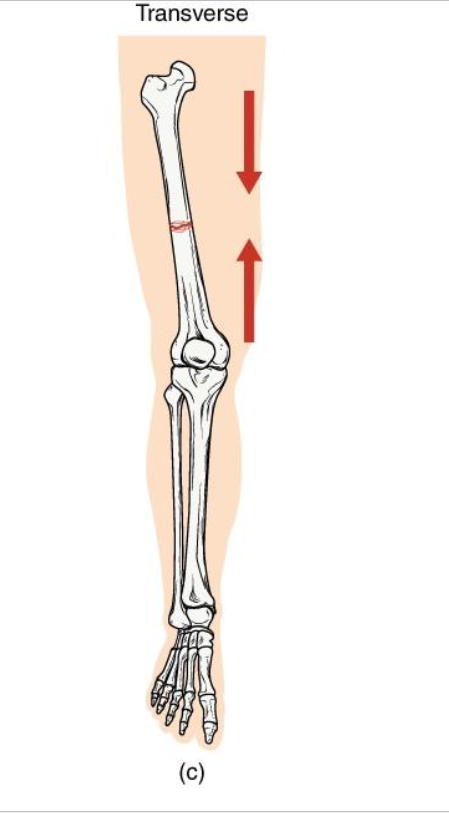

Transverse Fracture

Definition: Straight horizontal break across the bone shaft

Mechanism: Perpendicular force to long axis (ex: direct impact)

Clinical note: Often stable if bone ends align well: heals predictably with immobilizaton.

Key Concept: compression or bending directly across bone.

<p><strong>Definition: Straight horizontal break</strong> across the bone shaft</p><p><strong>Mechanism</strong>: <strong>Perpendicular force t</strong>o long axis (ex: direct impact)</p><p><strong>Clinical note</strong>: Often stable if bone ends align well: heals predictably with immobilizaton.</p><p><strong>Key Concept: compression or bending directly across bone.</strong></p>